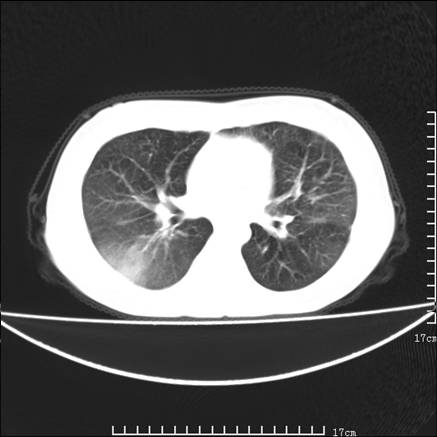

女,46岁,患胃溃疡多年,溃疡大小约1.0cm左右,后于5年前手术,病理为胃癌。主诉:半月前感冒后胸闷,气短,有咳嗽,无明显咳痰,无发热。偶有腰背部不适。

以下为高分辨扫描图像

双肺散在的 磨玻璃样及片状渗出性病灶,界限模糊。考虑:双肺感染!

双肺小叶间增厚,双肺散布粟米影和磨玻璃状影,以双肺上叶为重。结合病史考虑转移(癌性淋巴细管炎)可能性大。